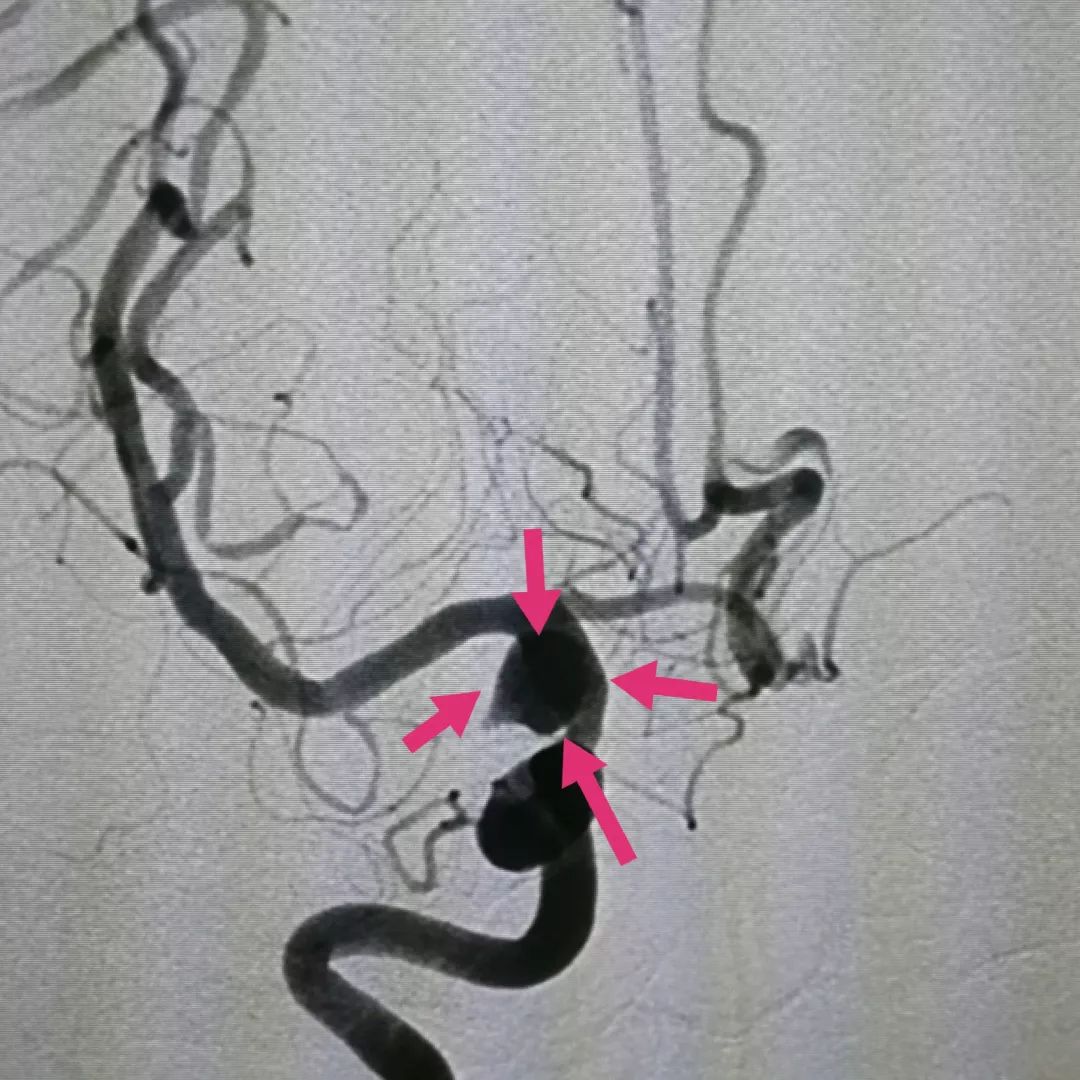

图三:另一角度2D造影看到动脉瘤位于后交通部位,所以称为后交通动脉瘤